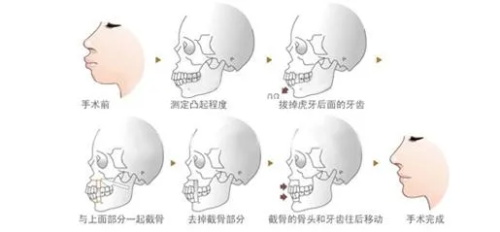

面诊那天,医生拿着我的CT片,指着骨头说:“你这是上颌前突+下颌后缩,得做双颌手术——上颌截骨后移,下颌截骨前移。”我听得云里雾里,只问了一句:“能让我侧脸不凸吗?”医生笑:“术后你的侧脸会立体很多,但得做好心理准备:前三个月肿得像猪头,半年才能正常吃饭。”我咬咬牙:“做!”

术后前三个月,我像“养伤正规户”——每天喝粥、吃蒸蛋,连苹果都得打成泥。第四个月开始,能嚼软饭了,但硬的东西还是不敢碰。第六个月复查时,医生拿着我的对比照说:“侧脸变化非常大,上颌收了5毫米,下颌前移了3毫米,现在比例很协调。”